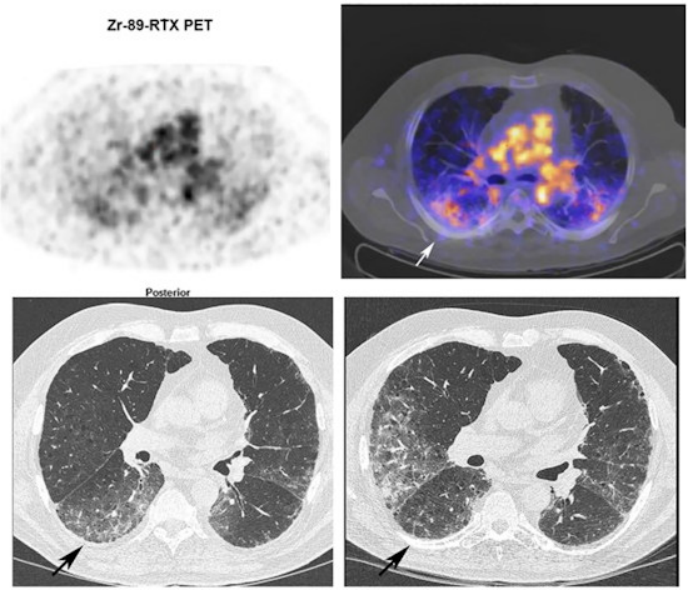

一例65歲纖維化非特異性間質性肺炎相關類風濕性關節炎患者的Zr-89利妥昔單抗PET/CT和HRCT(病例3)。Zr-89利妥昔單抗PET(左上)軸位PET圖像(右上)融合Zr-89利妥昔單抗PET/CT。PET基線時的HRCT(左下)和一年后的HRCT(右下)。PET/CT和HRCT之間的軸向視圖不完全匹配,因為HRCT是用吸氣命令執行的,而PET/CT處于靜止狀態。Zr-89利妥昔單抗活性更集中在下葉。Zr-89利妥昔單抗的中央區域與HRCT毛玻璃更相關;例如,見右肺下葉毛玻璃區域。利妥昔單抗治療一年后的HRCT在該區域未顯示該區域有任何毛玻璃。然而,在下葉的HRCT出現了新的毛玻璃區。患者的肺功能保持穩定。圖片由《歐洲核醫學和分子成像雜志》通過CC BY 4.0提供。